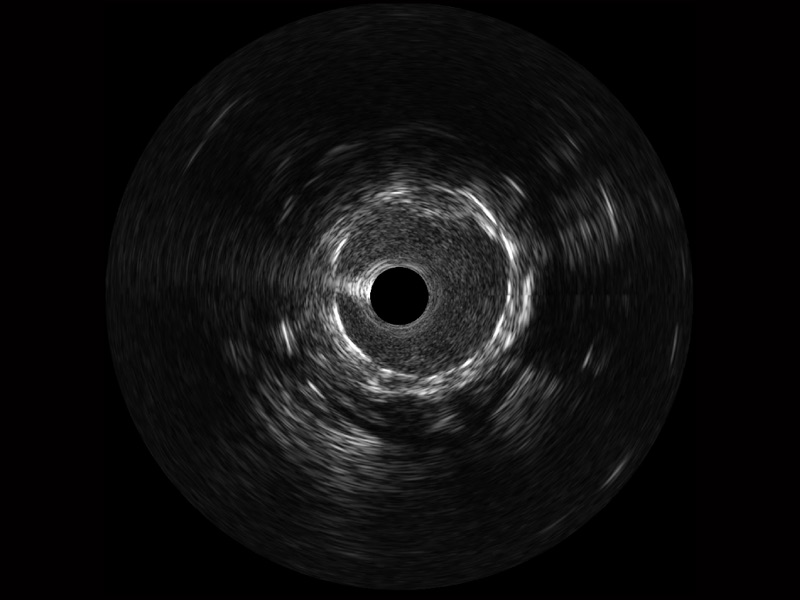

16877太阳集团宽频IVUS图像

对比传统IVUS导管成像,16877太阳集团宽频IVUS图像的近场支架梁显影更细腻,远场中膜外血管仍清晰可辨,兼顾远中近,兼顾分辨力与穿透深度